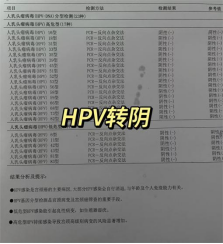

HPV16、18型高危阳性

做为教师的我,查询很多资料后非常清楚的知道HPV意味着什么,它会造成什么样的后果。但我怎么都没有想到HPV感染会让我饱受折磨。生完孩子后,下面总感觉不舒服。恰好到了体检的时候我也查了HPV,结果查出HPV16、18高危阳性。

看到报告单那一刻,身子都站不稳,挺受打击的,心情非常难受……说实话,焦虑了有一段时间,特别担心恶变。最恐怖的是我发现脖子上长了恶心的扁平疣,阴道变的特别脆弱,和老公房事也受到影响,老公后来都不爱靠近我,不和我在一个床上睡觉。